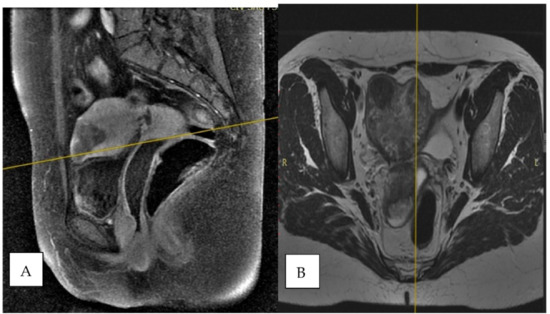

2. Case Report